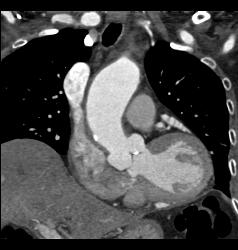

Supravalvular Stenosis and Prior Myocardial Infarction